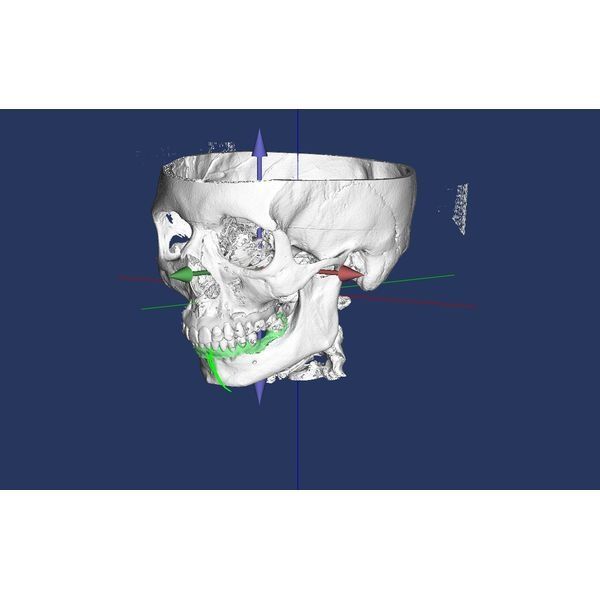

Конусно-лучевая компьютерная томография (КЛКТ) показала:

- очаги разрушения костной ткани в области корней зубов 2.7 и 1.7 — кисты, периодонтит;

- почти идеальное строение левого сустава — суставная головка округлая, с чёткими границами, но суставная щель заметно меньше нормы, т. е. челюсть смещена назад и вверх;

- изменения в правом суставе — деформация суставной головки в сочетании с узурами (эрозиями), участок перестройки костной ткани с «клювовидным» выступом, смещение головки назад;

- однородное заполнение большинства корневых каналов рентгеноконтрастным материалом.